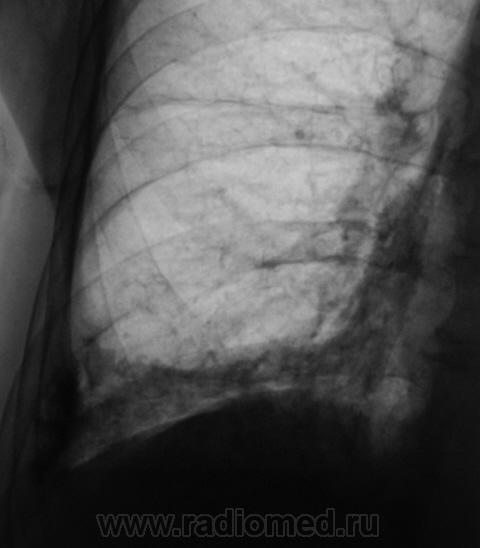

Пациент направлен на рентгенографию ОГК.

А томограмм нет. Просто демонстируется обызвествленная плевра.